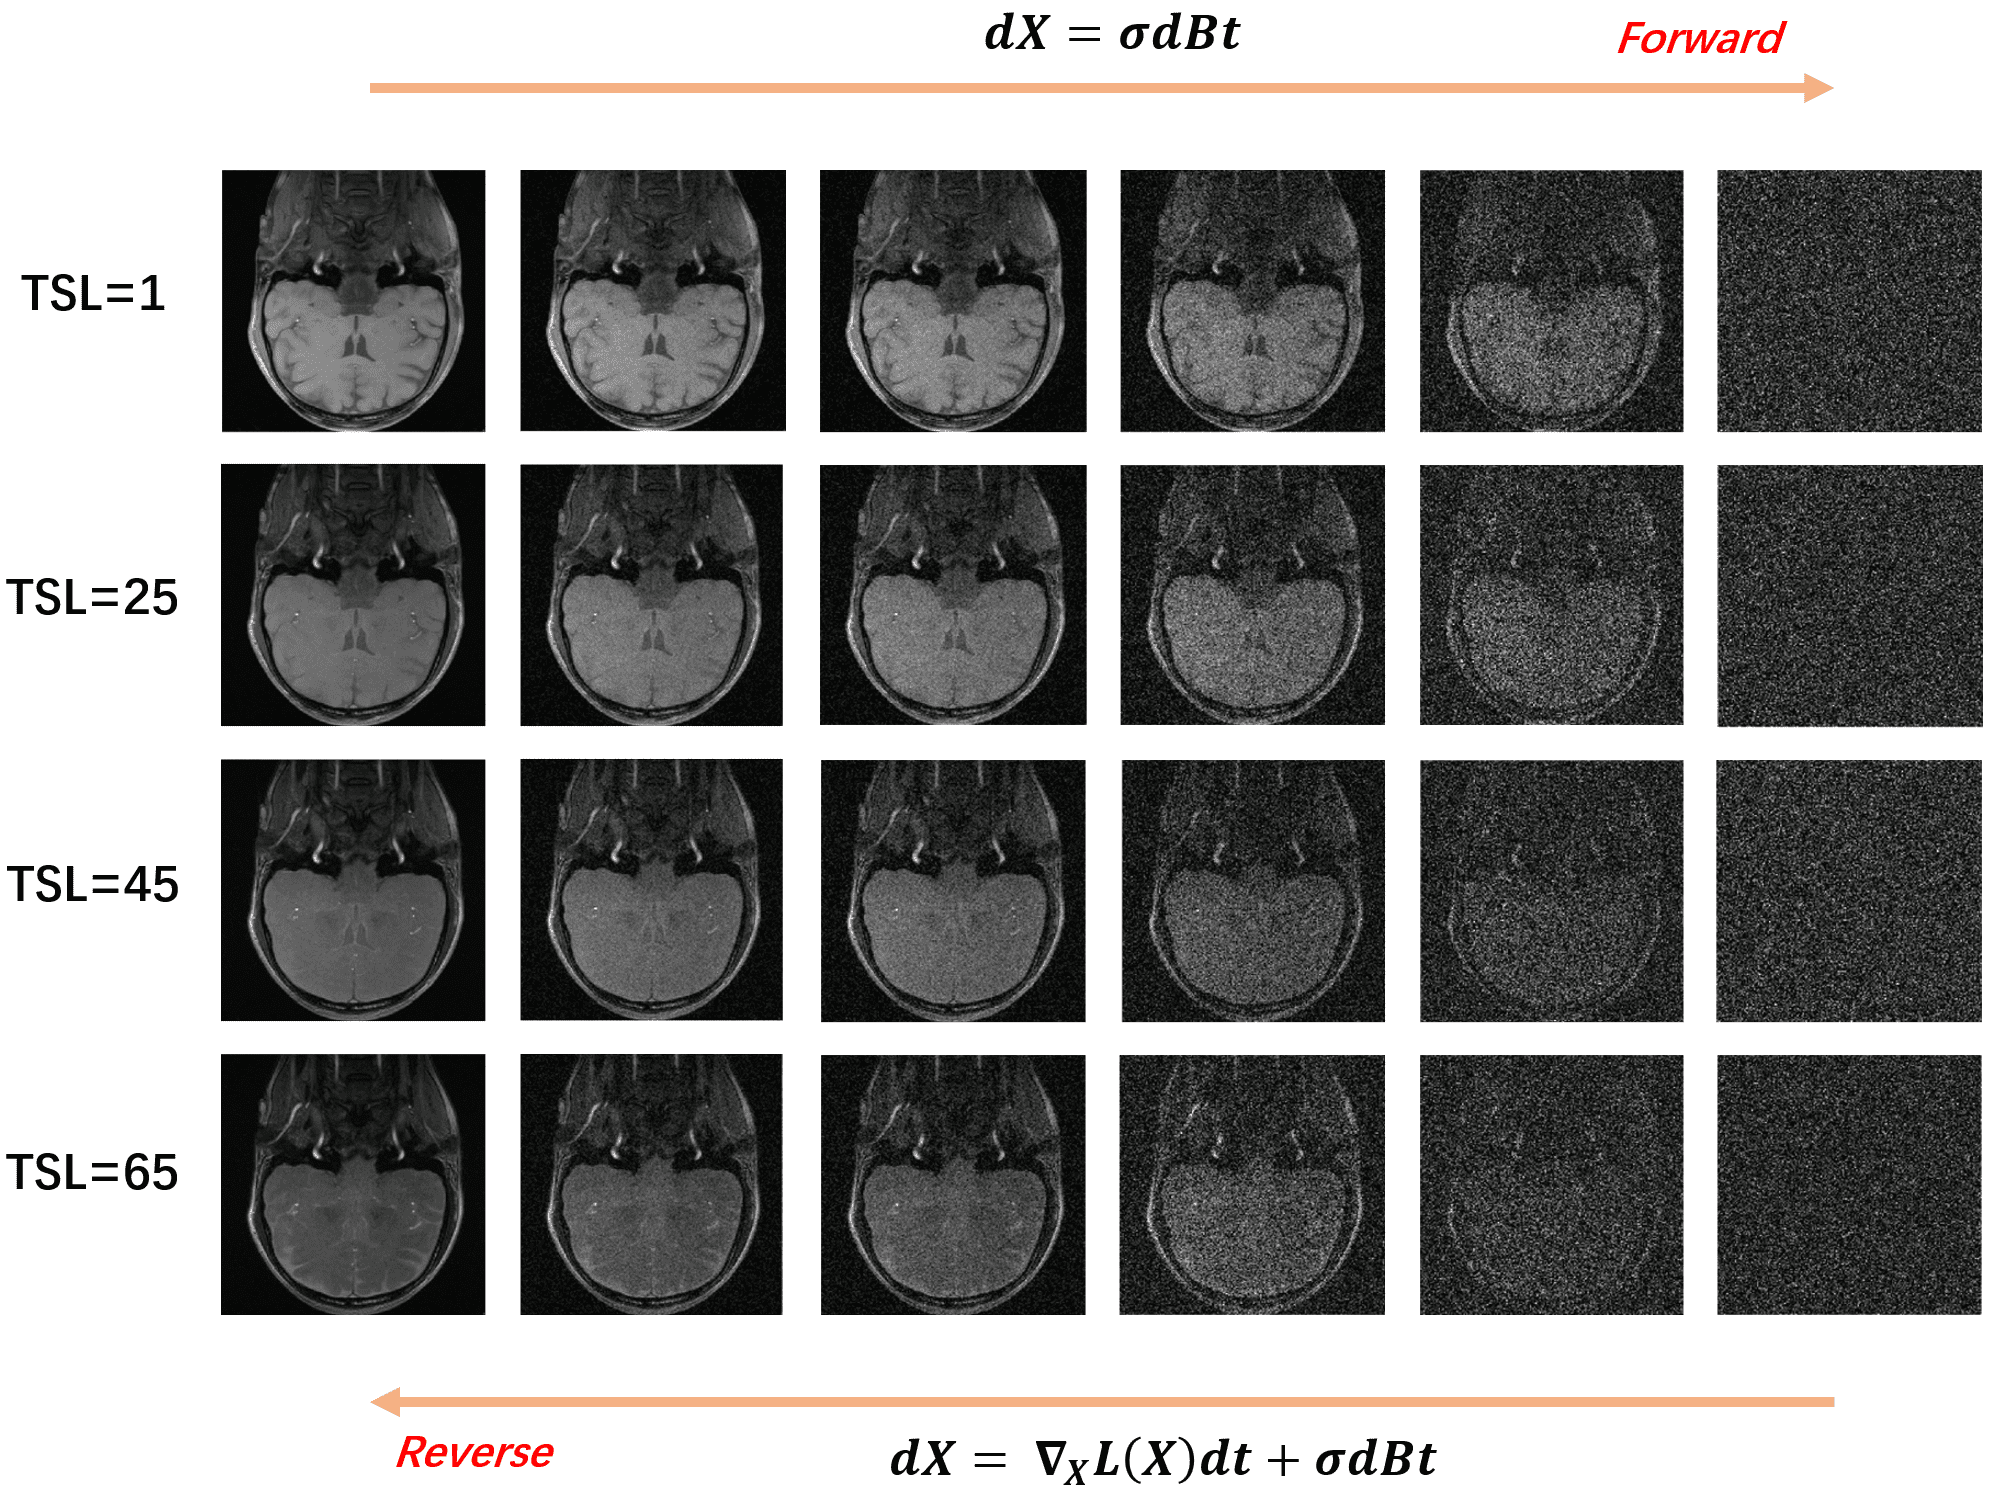

A schematic diagram of the bidirectional process is given in Fig. 1. The weighted images corresponding to different TSL are perturbed with Gaussian noise of differentintensities. The results in Fig.2 show that the uniform pattern has a certaintranscendence relative to the random pattern in terms of artifact-free. From T1rho maps by exploiting curve fitting, the proposed method is capable of quantification of T1rho relaxation times in uniform pattern with 8-fold acceleration.

Fig.1 Overall block diagram including Gaussian kernel perturbation and sample generation. Transforming T1rho data to a simple noise distribution can be accomplished at various times. The gradient of the learning joint data distribution given in the figure goes in the forward perturbation process applied in the reverse Langevin dynamic sampling.